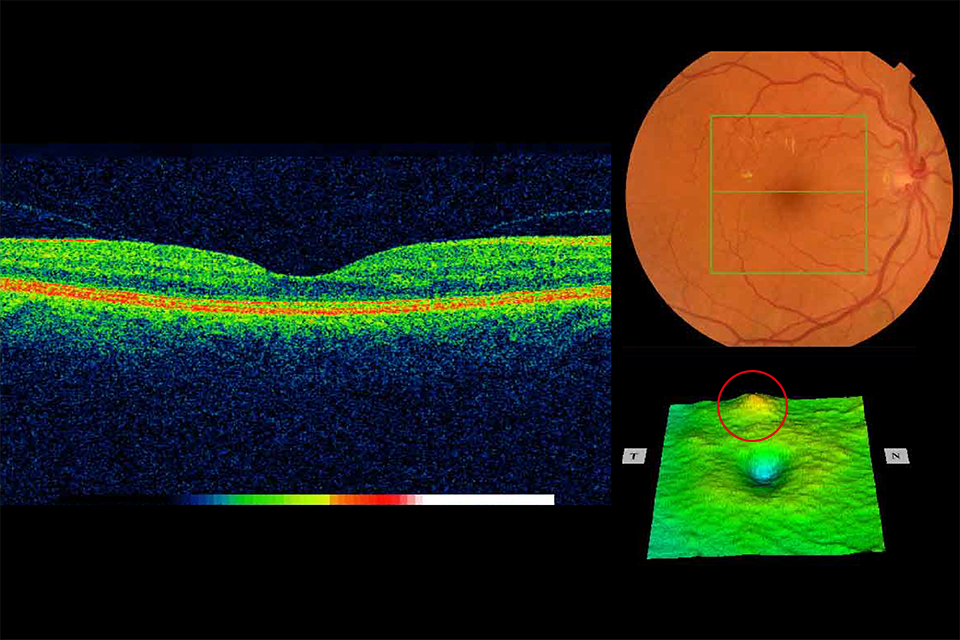

1. High risk maculopathy

High risk maculopathy is defined as macular exudation (circinate) greater than 1/2 disc area, within 1 disc diameter (DD) of the fovea and a drop in visual acuity in this eye to less than or equal to 6/12.

OCT image of retina showing high risk maculopathy